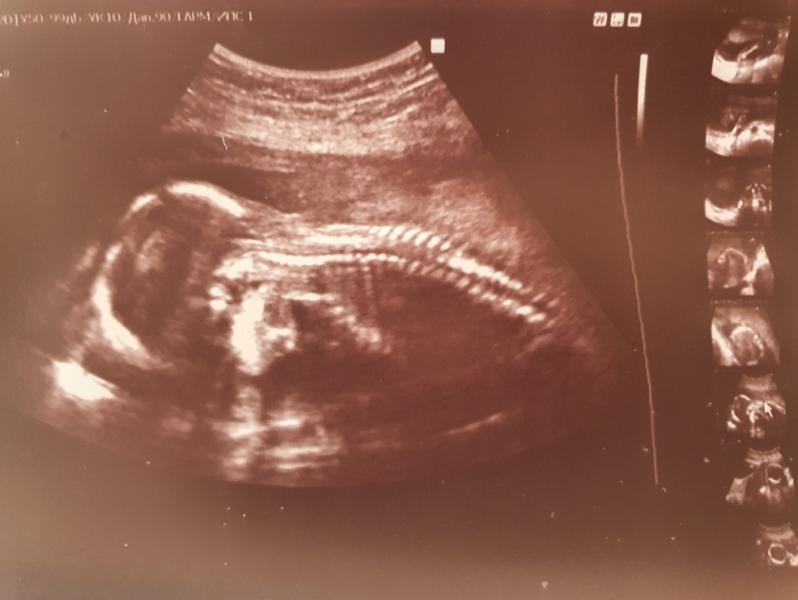

2 скрининг подтвердил мальчика🥰

19 недель и 1 день. Кроха 280 грамм и всё в норме😌